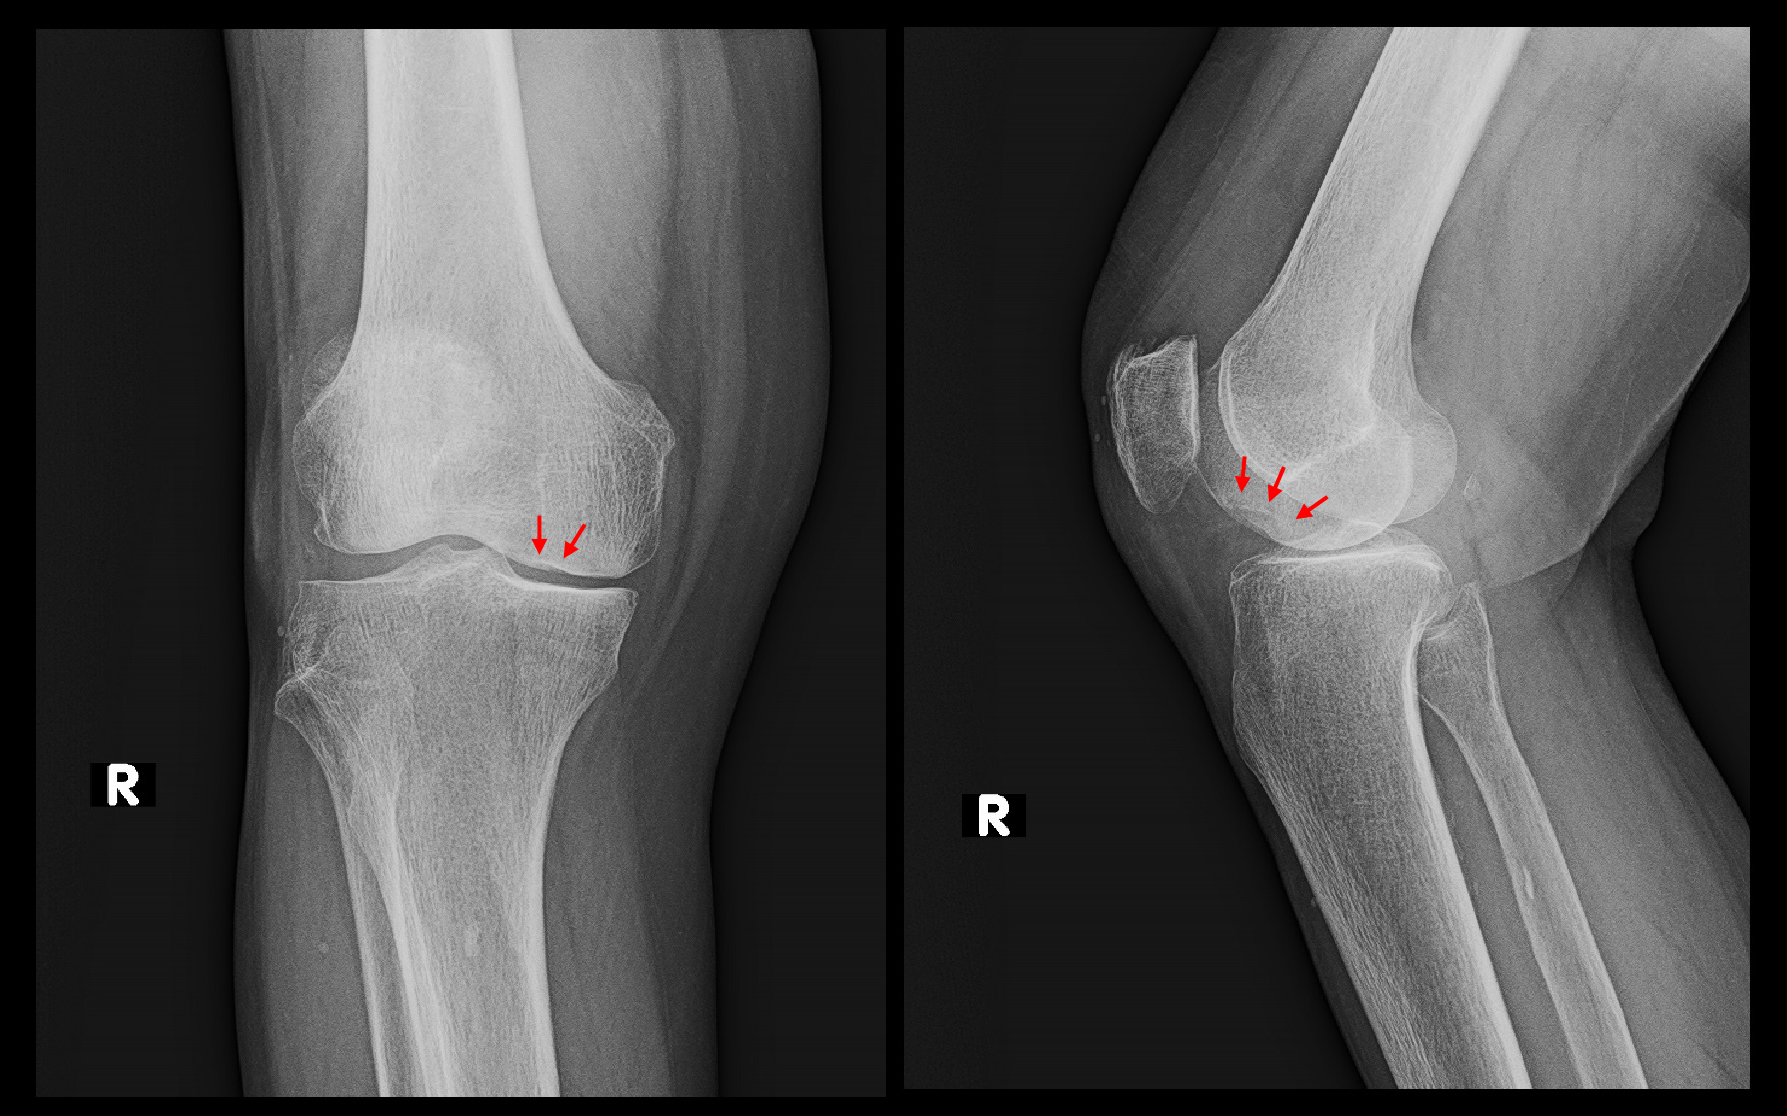

68才女 Xp2.jpg

この患者さんの場合も投薬とヒアルロン酸製剤関節注射で平成30年3月17日まで治療を続け、右膝痛は軽減し終了となりました。約半年間の治療期間となります。初診時、右膝のレントゲン像は異常を認めませんでしたが、5週後には壊死部の内顆部分の骨のラインは平坦化し骨が多少陥没したことが窺われます。治療終了時にはさらに陥凹は進行しています。骨の陥凹は進行しましたが、痛みは落ち着きました。